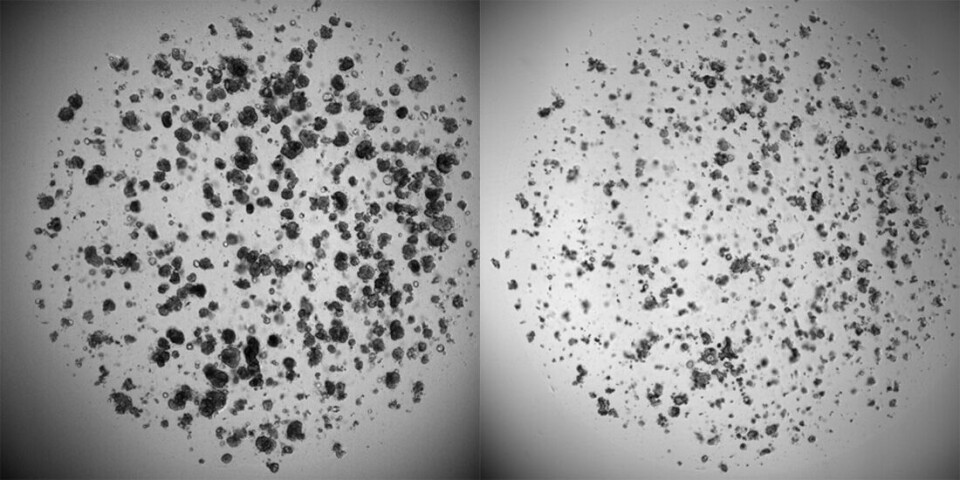

Dette er mini-svulster som vokser på laboratoriet, hentet fra en pasient med tykktarmskreft. – Målet er å videreutvikle teknikken til å kunne oppdage forskjeller som er av betydning, men som et menneske ikke ville lagt merke til ved tradisjonell lysmikroskopi, sier lege og sivilingeniør Flobak. (Bildet er tatt av forsker Christa Ringers som del av hennes arbeid ved NTNU)

Kreftceller på laboratorier. Til venstre ser vi kreftceller som har vokst i en uke uten tilsetning av medisiner. Til høyre ser vi kreftceller fra samme pasient etter å å ha blitt utsatt for cellegift. (Foto: Evelina Folkesson / NTNU / St. Olavs hospital / SINTEF)